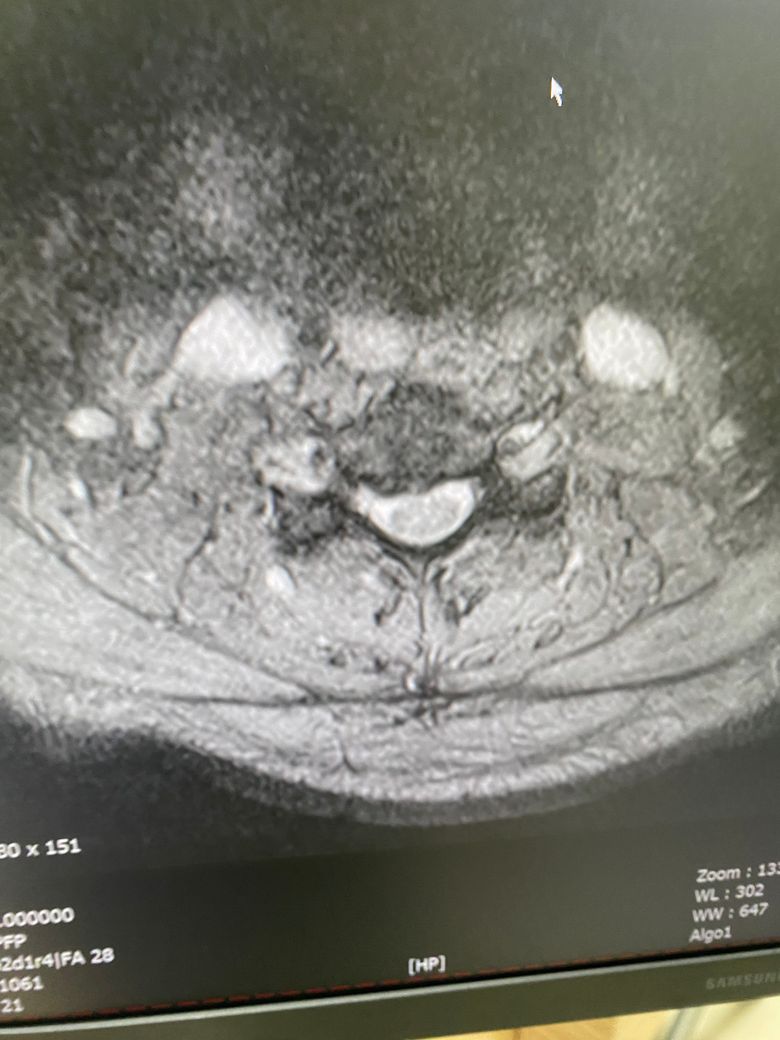

• 3번 째 사진

현재 디스크에 단계지만 여기서 중요한건 디스크가 신경을 건드려서 저림 증상 또는 통증을 동반하느냐도 큰 중요한 문제 중 하나입니다.

디스크가 많이 튀어나와도 생리학적인 이유로 신경을 건들지않을수도있고, 디스크가 조금 튀어나왔지만 생리학적인 부분에서 신경을 건드리는 경우도 많기에 이 부분은 전문의와 좀 더 자세한 설명을 들으시면 좋을거같습니다.

• 올리신 사진 세 장만 가지고 정확하게 어떻다 이야기 하기는 어렵습니다만, 디스크가 명확하게 돌출이 되어 있기는 하지만 신경을 누르는 정도가 딱히 심해 보이지 않습니다. 해당 사진들만 보았을 때에는 심각한 수준의 디스크로 보이지는 않습니다.